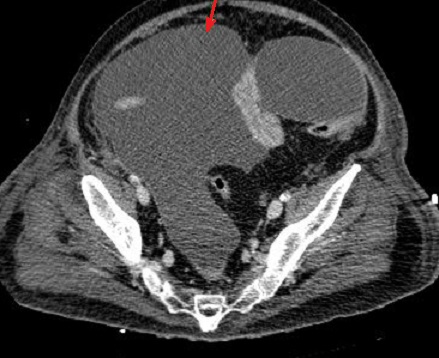

Aspect ascitique dans

la region pelvienne , complication d'une pancreatite

necrosant hemorragique |

Et une epanchement pleuraux

est le plus frequemment a gauche |